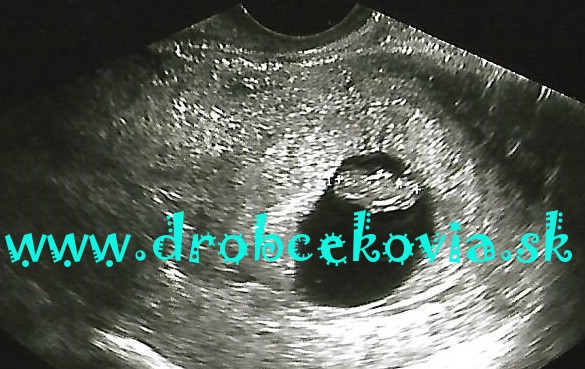

Takže vlastne až v tomto mesiaci som sa ubezpečila, že som naozaj tehotná. Okrem pozitívneho tehotenského testu mi to potvrdil aj gynekológ. Na sone ma však vystrašil slovami: „Mám pre Vás dobrú aj zlú správu“... Hlava sa mi zatočila, zalapala som po dychu, spýtala som sa ho najskôr na tú zlú. Odpoveď znela: „Zlá je, že je tam len jedno, dobrá je, že ste tehotná...“. Ten teda má svojský zmysel pre humor...

Správu o tehotenstve sme si s manželom zatiaľ nechali len pre seba, po gynekologickej prehliadke s prvým obrázkom v ruke sme to oznámili aj deťom. Starší syn vo veku asi 4 rokov začal žobroniť po súrodencovi. Vždy mi vravel, že chce mať dvoch – bračeka aj sestričku s dodatkom „neboj mami, nemusia byť naraz“. Keď k nemu ako 7,5 ročnému pribudol brat, rýchlo svoje prianie zmenil so slovami „keby som vedel, že bude revať, tak ho nechcem“. Tento raz mu to ako takmer 11 ročnému začínajúcemu puberťákovi už bolo jedno, vedel že to neovplyvní a už len sucho skonštatoval že „dúfam, že mi nebude stále brať lego ako Aleš“. Menší sa na bábätko teší, nevie ešte čo ho čaká 😉.